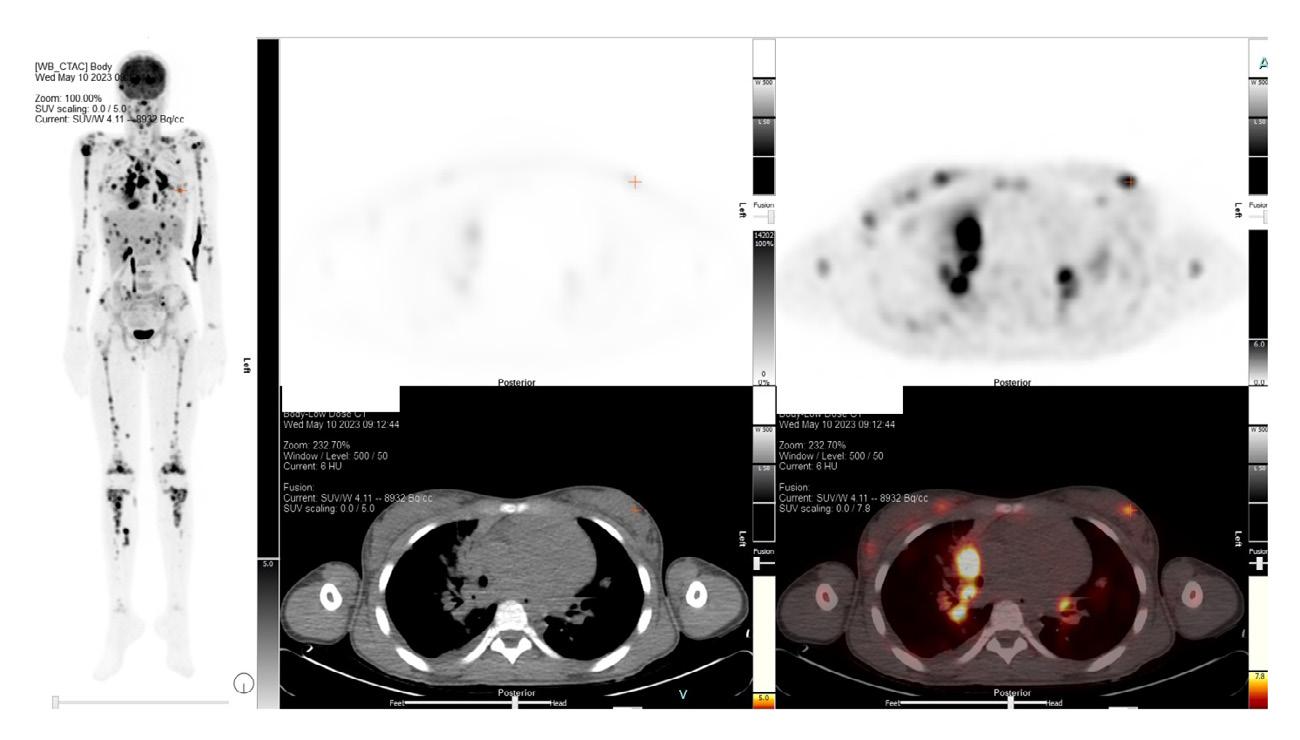

Cette dernière se présente au TEP-CT. Nous lui avons injecté une dose de 4,11mCi de F18-FDG et n’avons utilisé aucun agent de contraste pour la mise en image.

Sur les images du TEP-CT (figure 1), on peut constater plusieurs adénomégalies hypermétaboliques. Sachant qu’un ganglion normal mesure environ 1 mm, sur les images de la patiente, on trouve un ganglion situé latéralement à la trachée mesurant 18,0 mm avec un SUV max de 13,3. On constate aussi plusieurs foyers hypermétaboliques au niveau du tissu mammaire de façon bilatérale, plusieurs nodules pulmonaires, dont un avec un SUV max de 9,1, une atteinte rénale ainsi qu’une hépatomégalie avec au moins cinq foyers hypercaptants. De plus, il y a pré sence d’un

infiltrat pulmonaire très hypermétabolique avec un SUV max à 15,6. On trouve également plusieurs foyers hypercaptants osseux, dont un à la tête humérale droite avec un SUV max à 12,2, des foyers intramusculaires et même une suspicion d’atteinte du muscle orbitaire latéral droit. Il y a présence de foyers cutanés hypercaptants à la région fessière ainsi qu’aux cuisses, mais ces derniers sont plus discrets. Selon notre nucléiste, « Le tout laisse suspecter une atteinte néoplasique leucémique ou lymphomateuse sous-jacente ».

l’échantillon. Toutefois, au lendemain de notre examen, la fillette subit une biopsie de la lésion sous-cutanée de la portion supérieure de la fesse gauche, tel que suggéré par la nucléiste.

En attendant le rapport de la pathologie, l’équipe traitante a organisé une réunion multidisciplinaire afin de discuter du diagnostic. Serait-ce vraiment le syndrome d’activation macrophagique ? Une douzaine de cas vus en médecine nucléaire ont été révisés et aucun ne se présentait avec ce tableau. L’atteinte multiple, surtout cutanée, serait très atypique pour une histiocytose à cellules Langerhans . Les différents sous-types de déficit immunitaire sont également peu probables.

L’utilisation du TEP-CT joue un grand rôle dans le diagnostic de la leucémie, surtout dans le but d’évaluer l’atteinte extramédullaire, d’évaluer les rechutes de la maladie ainsi que l’activité inflammatoire qui y est associée. Il arrive donc souvent que nos patients recevant un diagnostic de leucémie se présentent avec de la fièvre qui perdure. Cependant, la biopsie de la moelle osseuse reste l’examen de référence pour poser ce diagnostic.

Alors, qu’a-t-on trouvé au rapport de pathologie de la biopsie du nodule sous-cutané ? Selon les analyses, il s’agit d’un lymphome T à grandes cellules anaplasiques, ALK-positif et CD30-positif. Le premier échantillon de la moelle osseuse a été ressorti pour effectuer une analyse plus profonde et le même infiltrat y a été retrouvé.

deux formes : ALK-positif et ALK-négatif. La différence entre les deux réside dans la présence ou non de la protéine appelée anaplastic large cell kinase (ALK). Les patients qui présentent un ALK-positif sont souvent plus jeunes et répondent mieux au traitement.

Malheureusement, lorsque les organes tels que les os, la peau, la moelle osseuse, les poumons et le foie sont atteints (ce qui arrive chez environ 70 % des patients au moment du diagnostic), cela indique un stade avancé de la maladie (stade 3 ou 4). Dans le cas de notre jeune patiente qui présentait une infiltration pulmonaire, une autre biopsie a été effectuée du

liquide pleural où on a pu constater la présence de cellules de grande taille ayant les mêmes marqueurs ALK-positif et CD30 que dans ses autres biopsies.

En conclusion, un diagnostic précoce assure un traitement efficace à l’enfant. Il est toutefois facile de constater que les symptômes peuvent être associés à des pathologies différentes. Or un retard dans la prise en charge par une équipe spécialisée risque d’augmenter les effets indésirables de la maladie et même de diminuer la survie. La prise en charge du patient par une équipe multidisciplinaire (dont celle de l’imagerie médicale) est donc primordiale.